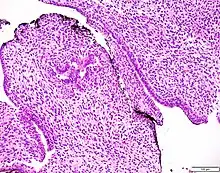

Prostatic stromal tumour of uncertain malignant potential. H&E stain.

Prostatic stromal tumour of uncertain malignant potential (PSTUMP) is a rare tumour of the prostate gland stroma that may behave benign or like cancer.